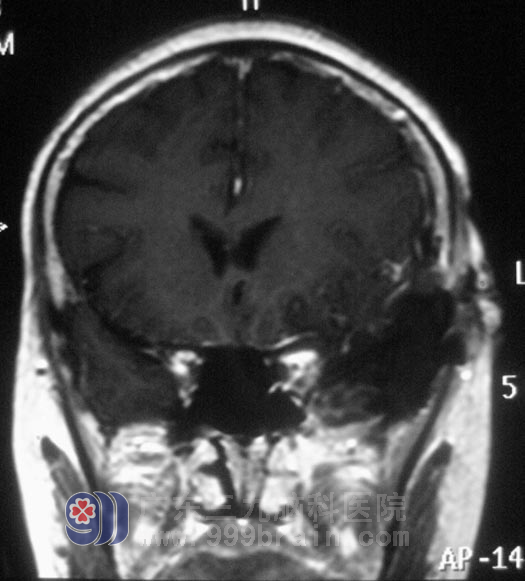

颈椎MR提示“颈4/5、5/6、6/7椎间盘突出”,头颅MR示“左侧蝶骨嵴脑膜瘤,大小约2.8cm×2.9cm×3.1cm”。家人回想起两年前,黄女士就开始出现左眼视力下降,偶有头晕,并没有引起重视,知道这个结果后肠子都悔青了。

11月23日,由广东三九脑科医院综合神经外科 鲁明主任主刀,在全麻下行左侧蝶骨嵴脑膜瘤切除术+颅内压探头植入术,术中取左侧额颞弧形切口,在显微镜下见肿瘤呈灰白色,与大脑中动脉粘连紧密,予肿瘤全切,对视神经、动眼神经保护完好。术后黄女士经过一段时间的恢复,诉左眼视力较术前明显好转,肩周炎也在广东三九脑科医院得到了有效的治疗。术后病理结果:过渡型脑膜瘤 WHO I 级。http://www.999brain.com/